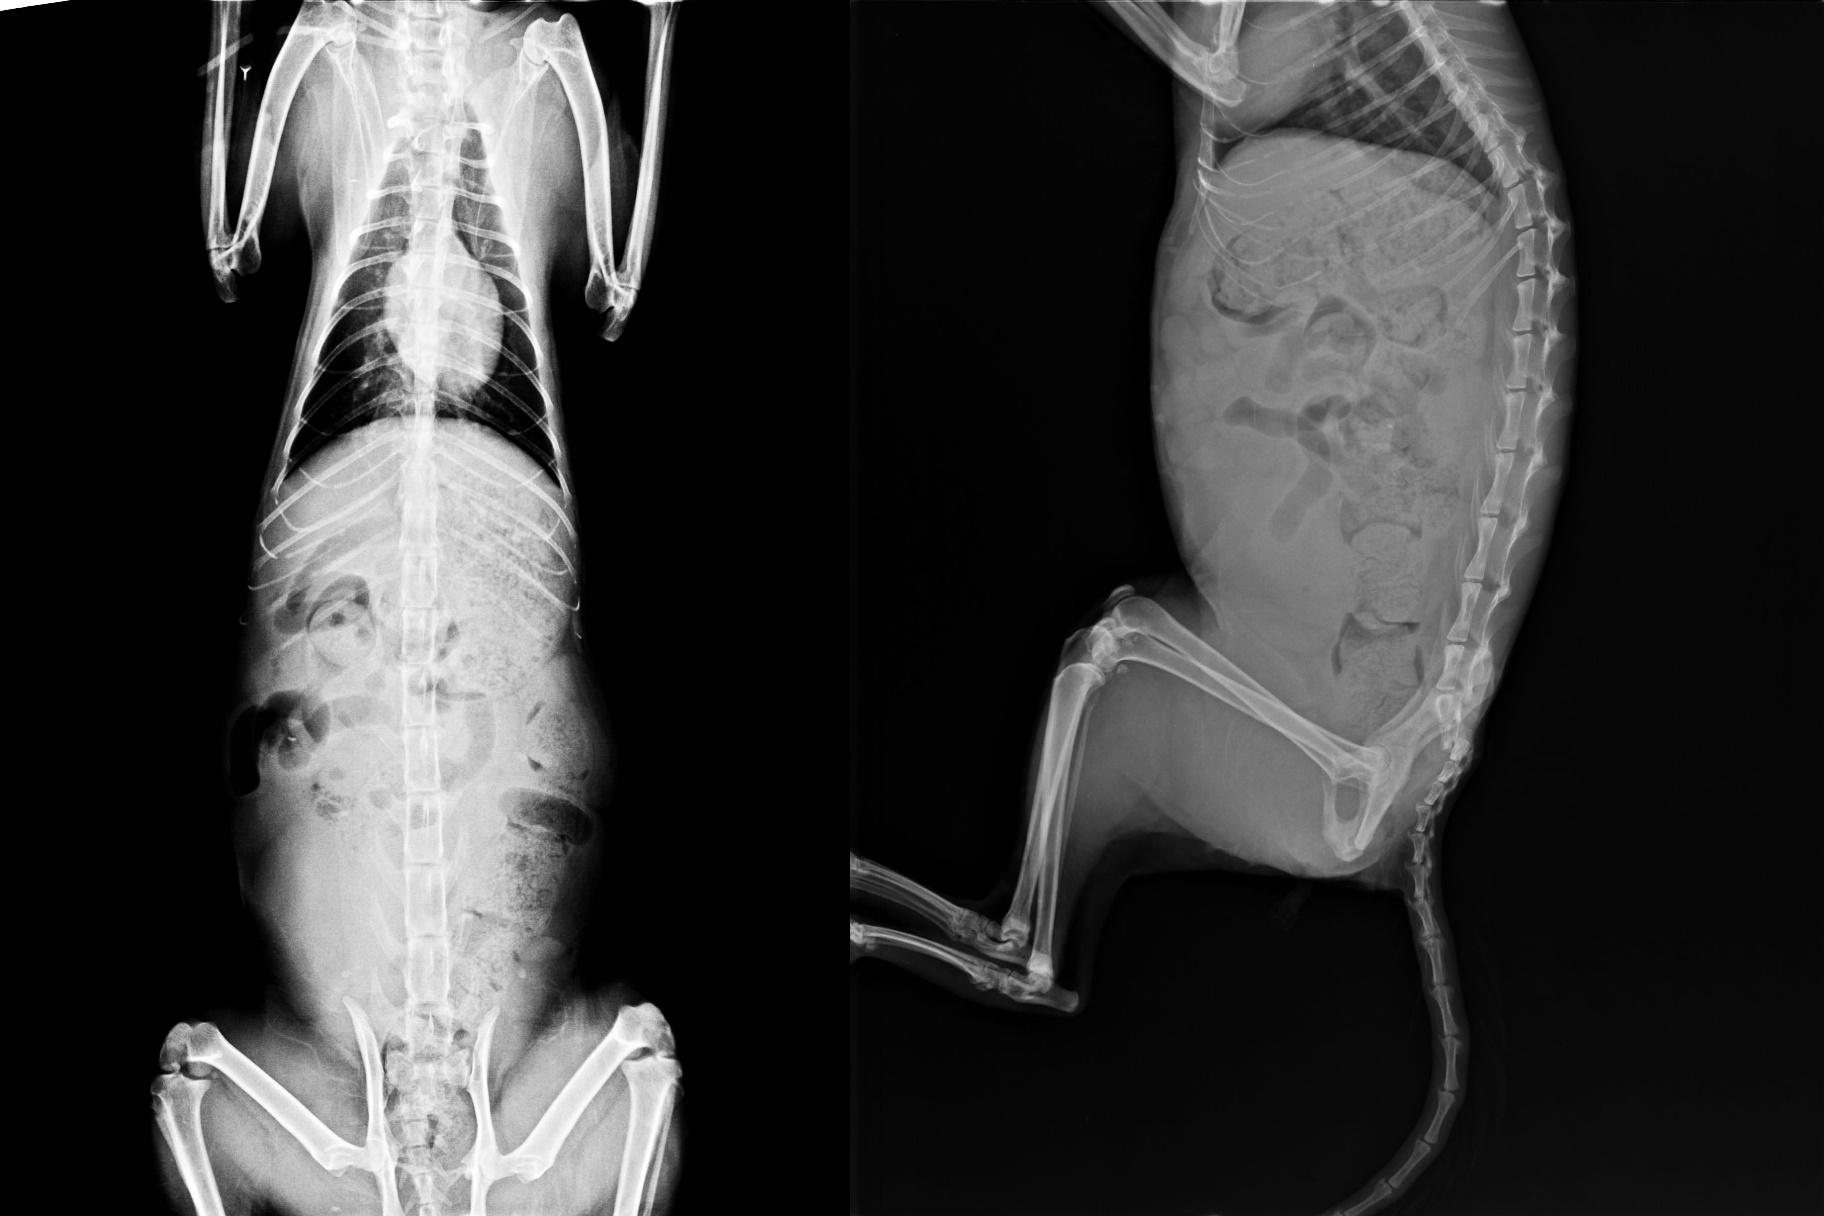

主題: 花喵媽媽 申請者姓名: hung 花色: 申請日期: 2014-01-15 11:25:23 申請者部落格: 申請者臉書網址: 所在縣市/合作醫院: 台北市/極光動物醫院 治療費用: 31770元 需求人數: 34人 已結案 (2014-03-24 18:18:12) 報名人員: Summer(已付款)、Cathy Kao(已付款)、tienhl(已付款)、Shih Ju Chiu(已付款)、Irene Meng(已付款)、張雅筑(已付款)、臺北市支持流浪貓絕育計劃協會(代KiKi報名)(已付款)、蔡秀芳、Becca Huang(已付款)、jenny(已付款)、Irene Chu(已付款)、波波(已付款)、SosaShen(已付款)、青蛙男(已付款)、Enid(已付款)、Pei-yan Wu(已付款)、Choco Chen(已付款)、Jackie Kang(已付款)、iMADOKA(已付款)、綺(已付款)、王千枝 x2(已付款)、張啟民(已付款)、Gary Chen(已付款)、Maggie Chen(已付款)、Mia Jheng(已付款)、imlosting(已付款)、Hamaji Lee(已付款)、Angel Chang(已付款)、Angel Chang、Teresa Kao(已付款)、Eucalyptus Wu(已付款)、Yao-Hsien Tseng(已付款)、lavinia(已付款)、小四 x2(已付款)、 候補人員: 動物病情說明: 這支花喵媽媽已經餵養了三年多了...她於日前突然不見了很久......之後終於回來了..但郤癹現...她的尾巴一直挺不起來..也在她身上聞到重重的尿味...直到近日在一之機會下看見他在清理身體時..略約看他的腹腔下方有傷口..加上有濃烈的腐臭味..才決定將她誘補送醫..送醫後才癹現...原來她因為骨盆腔有骨折而造嚴重的漏尿問題...造成下肢腹部皮膚潰爛... 動物近況說明: 花喵媽媽已經在經過了極光動物醫院三個星期的住院治療後..在腹部的潰瀾傷口已經完全復原...在精神及飲食上也都非常的健康及正常..我已於1月11日星期六將他接回自家照頺.但由於花喵媽媽目前在尾部有粉碎性的骨折.尚未完全痊癒.在醫生的建議下.目前先將花喵媽媽養在二個中型合併的大籠子內..以方便觀察花喵媽媽的漏尿及漏便問題..是否會再影響花喵媽媽的腹部再次潰瀾.....到目前已經過了5天了...一切都還好..也希望在這段期間的照頧中花喵媽媽可以早日康復...再次謝謝協會及醫院的醫生,護士及各位付出善心的朋友們....